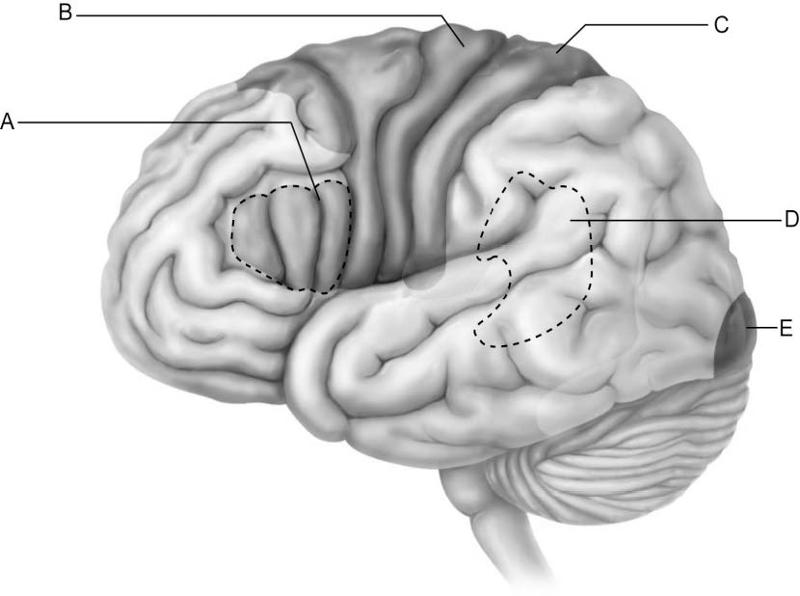

Which letter indicates the primary visual cortex, which receives

information from neurons in

the retina of the eye?

A)

A

B) B

C) C

D) D

E) E

E

Which letter indicates Broca's area, which controls the motor

movements necessary for

speaking?

A) A

B) B

C)

C

D) D

E) E

A

Which letter indicates Wernicke's area, which is important for

understanding spoken words?

A) A

B) B

C) C

D)

D

E) E

D

Which letter indicates an area that is characterized by huge neurons

known as pyramidal cells?

A) A

B) B

C) C

D)

D

E) E

B

Which letter indicates the primary somatosensory cortex?

A)

A

B) B

C) C

D) D

E) E

C